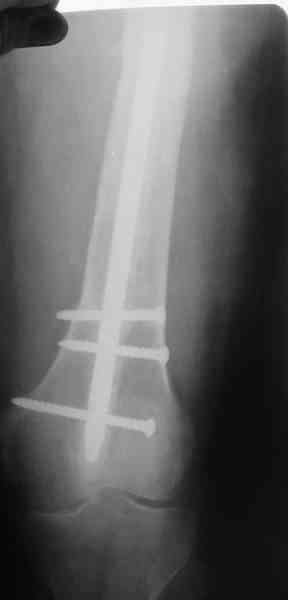

В настоящее время наш пациент ( см. http://weborto.net/forum/1177351385/) ходит с одним костылем. У него периодически открывается свищ на задне-наружной поверхности бедра с умеренным серозно-гнойным отделяемым. Температура тела и анализы нормальные. На рентгенограммах имеются признаки консолидации ложного сустава.

Иллюстрации:

1, 2, 3, 4 - рентгенограммы бедра от 8 августа этого года (через четыре месяца после операции);

Вчера наш пациент был на контрольном осмотре. Вроде все идет нормально. Рентгенограммы от 25 сентября 2007 г. (прошло 5 месяцев после операции) прилагаю.